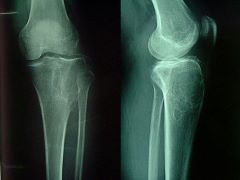

骨巨细胞瘤的病理学表现!骨巨细胞瘤有很少的部分都会发生肺转移,预后也很好,但是少数的患者可以通过手术得到治愈,也有转移灶长年保持不变或自行消退,然而,约有20%的肺转移病例,病情可能迅速发展,导致死亡。下面就介绍一下骨巨细胞瘤的病理学表现?

显微镜下所见其主要镜下特征是:形态单调的基质细胞,小而形态均一的多核巨细胞,丰富的血管以及明显的坏死。

基质细胞含有大的空泡样细胞核,核膜明显,其内含有一个或两个核仁,巨细胞由基质细胞融合而成,体积小而均一,细胞核的特征同基质细胞,病变组织经常由合胞体或巨细胞网络构成,很难辨别出基质细胞和巨细胞,这些细胞和血管一起即构成了有活力的肿瘤组织,其质地柔软易碎且呈红褐色。